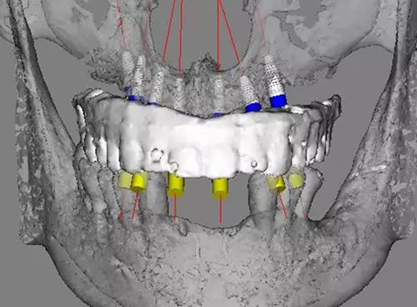

治療計(jì)劃及種植方案設(shè)計(jì)

患者骨高度嚴(yán)重不足,尤其是后牙區(qū),骨高度基本都只有2mm。按常規(guī)傾斜植入的方式也不可行,因此選擇在5號(hào)位通過(guò)內(nèi)提升方式植入植體。